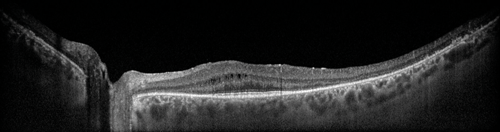

Figure 1: Wide-field EDI-OCT (OS) of patient with primary autoimmune retinopathy. Note the intraretinal cysts and enhanced view of the choroid. On Heidelberg Spectralis EDI, 55 degrees widefield, automated real time (ART) of 9.

Imaging of the choroid is becoming more accurate which is useful in diagnosing CSR, where a thickened choroid is found, and in some inflammatory conditions as a means of monitoring response to treatment [4]. This has become possible through the use of enhanced depth imaging OCT (EDI-OCT) technology, which was first described by Spaide et al. in 2008 [9]. This worked through the OCT apparatus being moved closer to the subject’s eye, creating an inverted image and with the relevant software re-orientated the image. This changed the peak sensitivity, from near the posterior vitreous as in conventional OCT, to the inner sclera. Now software correction allows this to be done automatically for EDI-OCT (Figure 1). Further developments such as the use of swept source OCT and longer wavelengths can provide a wider depth of resolution from the posterior vitreous to the choroid.